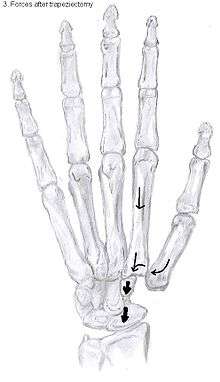

The large forces, which the CMC1 joint has to withstand, are considered to be another cause of CMC OA.[10] During daily manual activities, such as grabbing and pinching, the thumb is constantly being used. The forces generated by these movements have an enlarged impact on the CMC1 joint because of the leverage within the thumb. This makes the joint even more sensitive to wear and tear.[10]